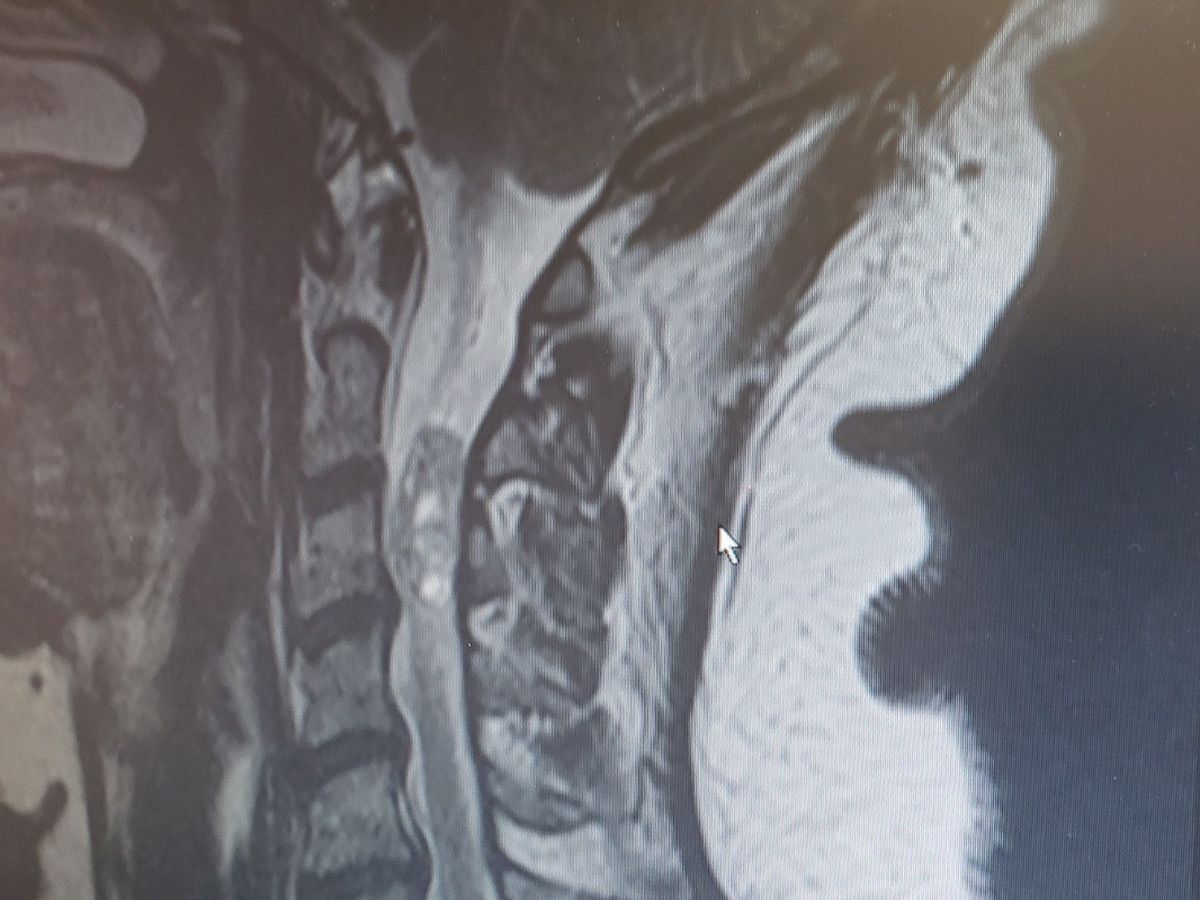

My mother had an MRI done in July and it was discovered that she had a tumor inside her spinal column and it was pressing on her nerves and its causing her massive amounts of pain. She cant sleep, barely eat, isnt recommended to work and now she cant drive. Her surgery is on the 13th of September, anything will help, please.